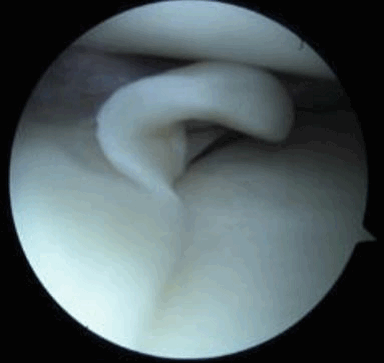

Для диагностики важна еще и форма мениска. В норме он в определенной плоскости имеет форму бабочки. Любые отклонения могут указывать на возможный разрыв.

Рис. 2. Эндоскопия коленного сустава. Неповрежденный медиальный мениск. Эндоскопическим способом осматривается свободный край мениска.